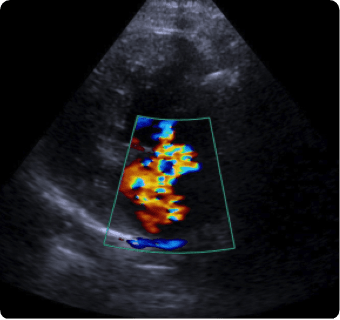

일산시티동물의료센터는 지멘스에서 개발한 고성능 프리미엄 초음파 장비인

Siemens Sequoia를 활용하여 심장, 복부 장기, 림프절 등의 구조물을 선명하게 구현하고,

미세한 해부학적 구조까지 정밀하게 확인할 수 있습니다.

이 장비는 대표적인 심장 질환인 이첨판 폐쇄부전증과 비대성 심근병증,

그리고 선천성 심혈관 질환인 동맥관 개존증, 심방중격결손, 심실중격결손 등을

진단하는 데 사용됩니다.

또한 급성 췌장염, 급성 신부전, 자궁축농증, 방광염, 요로결석, 소화기 이물,

비장종양 등의 질환을 진단하고, 환자의 상태를 평가하는 데에도 활용됩니다.